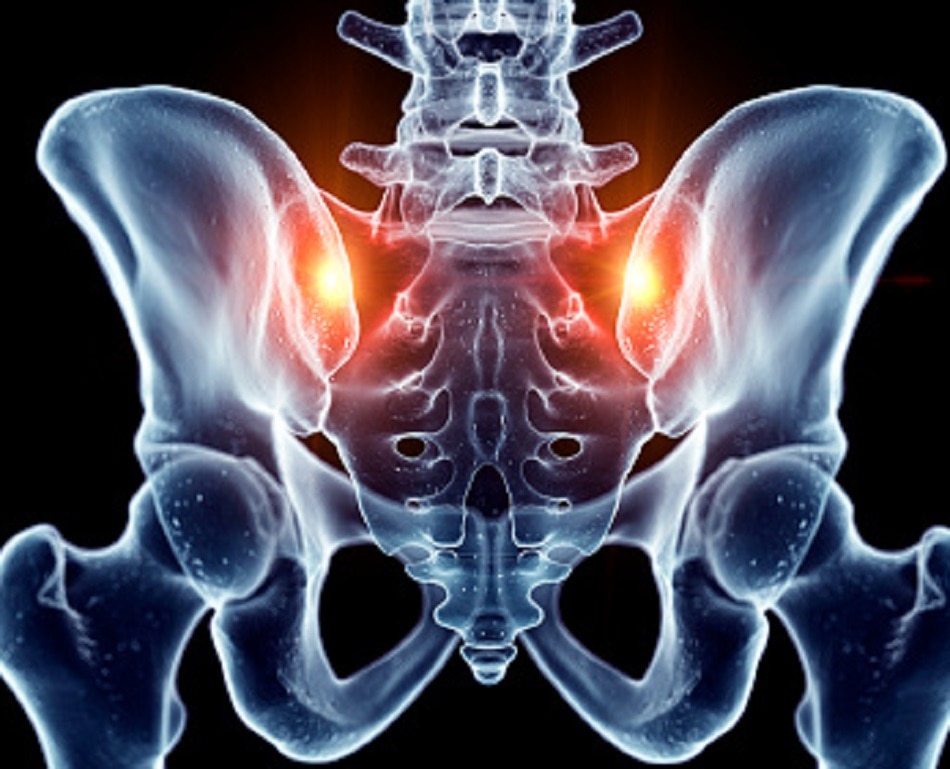

किन्हें हो सकती है AVN की दिक्कत- डॉक्टर्स कहते हैं कि लाइफ सेविंग ड्रग्स ले रहे लोगों में AVN की दिक्कत बढ़ सकती है. फेफड़ों में इंफेक्शन का जोखिम कम करने वाले स्टेरॉयड कूल्हे या जांघ वाले हिस्से में ऐसी परेशानी बढ़ा सकती हैं. हम कोविड-19 मरीजों की रक्त वाहिकाओं में स्टेरॉयड की वजह थ्रोम्बोसिस की समस्या भी देख चुके हैं. डॉक्टर्स का दावा है कि स्टेरॉयड पर रहने वाले रोगियों में AVN से पीड़ित होने की संभावना अधिक होती है.

Photo Credit: Getty Images

क्या हैं लक्षण- AVN के मरीजों में कई तरह के सामान्य लक्षण देखे जा सकते हैं. उन्हें कूल्हे और कमर में दर्द की समस्या हो सकती है. खड़े होने या चलने में भी परेशानी हो सकती है. जोड़ों में बहुत दर्द रहने लगता है. इसलिए शरीर में इस तरह के लक्षणों को बारीकी से देखें और समय पर जांच जरूर कराएं.